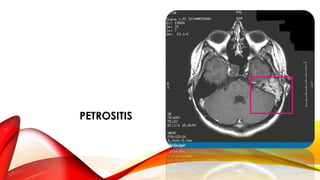

PETROSITIS

• Rara

• Puede ocurrir en Apex petroso no

neumatizado, esclerótico, diploico

• Diagnostico y cuadro clínico similar

a Mastoiditis